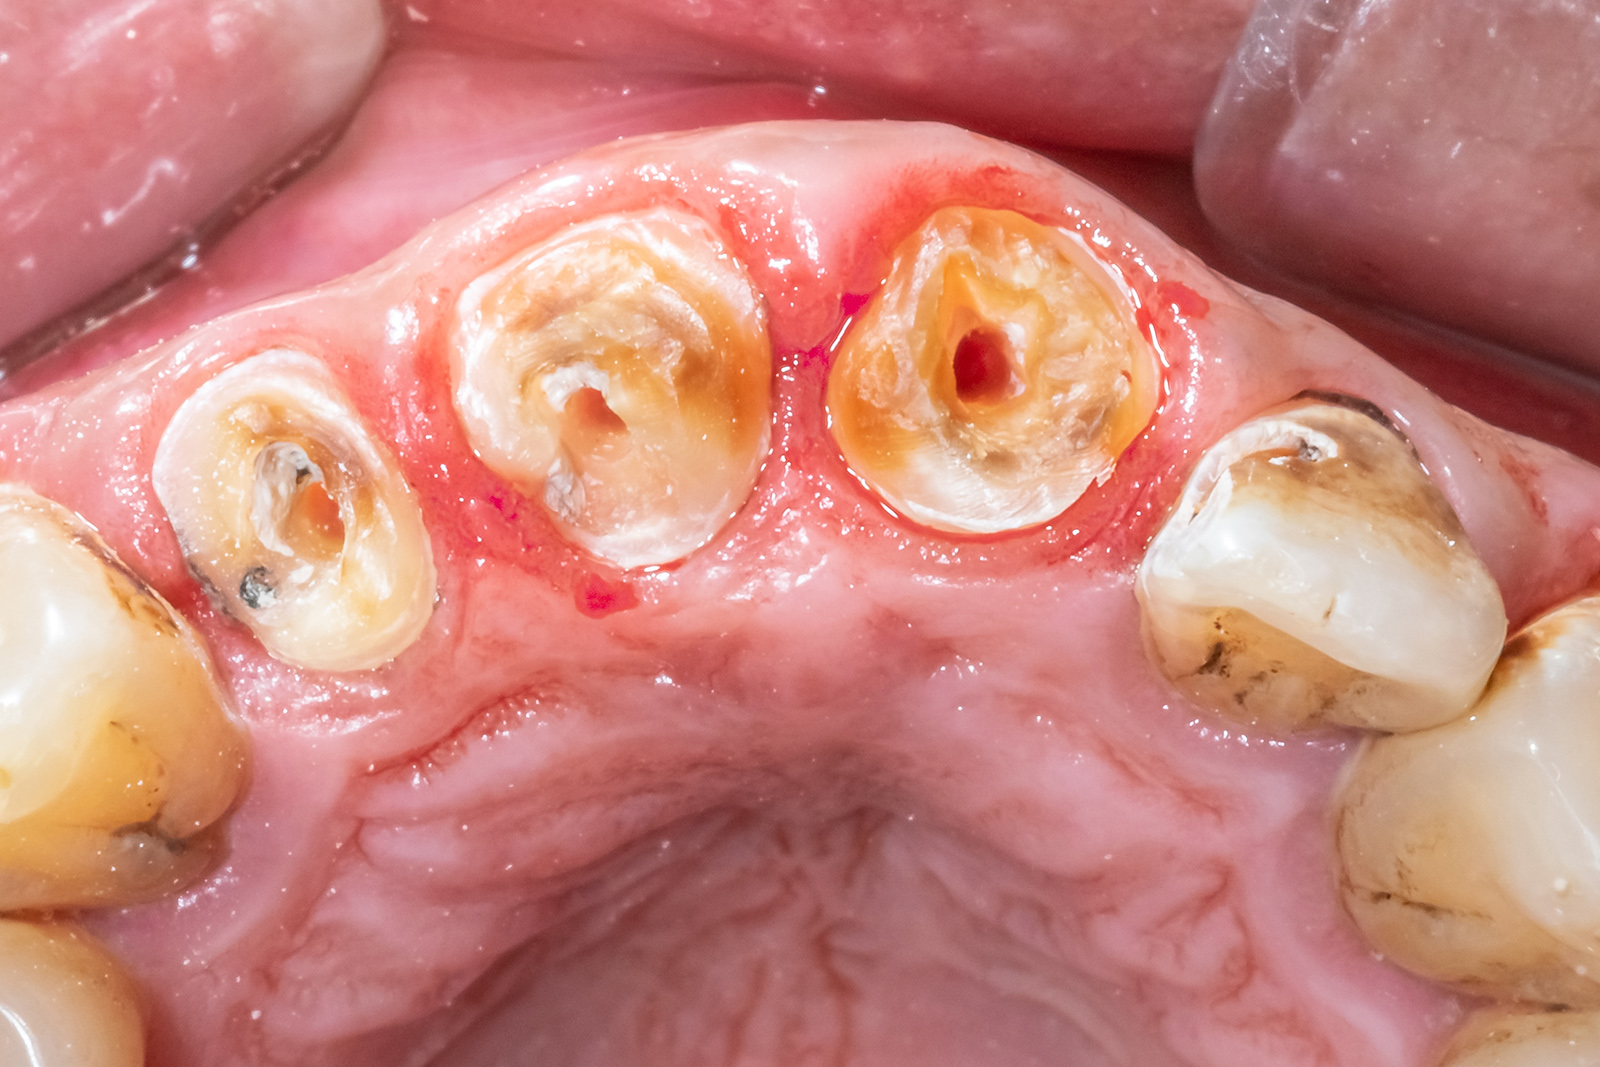

• 治療前

虫歯部分を赤く染める「う蝕検知液」

虫歯の治療では、う蝕検知液という検査薬を使います。

虫歯に感染している部分に反応して色がつくため、削る必要のある場所を確認しながら治療を進めることができます。

色がついた部分だけを削ることで、健康な歯をできるだけ残し、必要以上に削らないよう配慮しています。